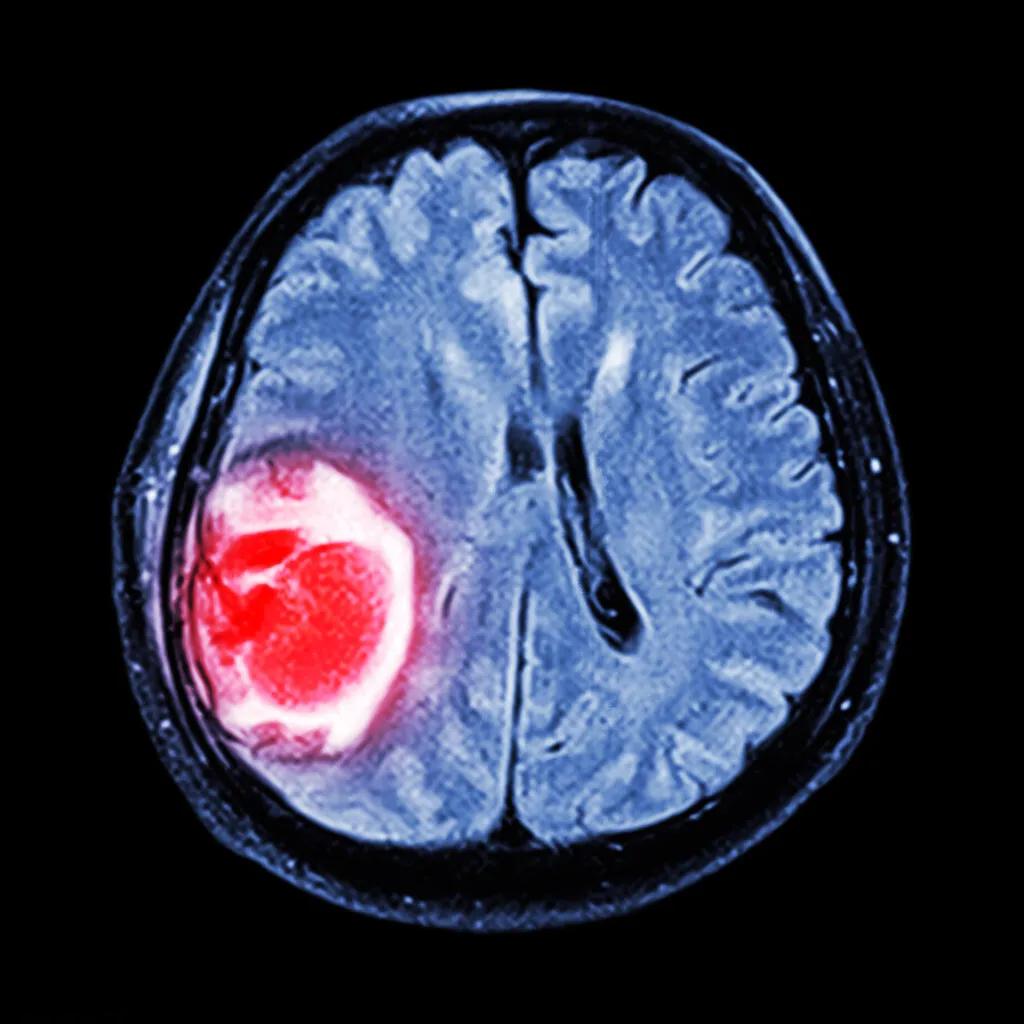

脑膜瘤是一种癌症吗? 答案是:不一定。脑膜瘤是起源于脑膜的肿瘤,它可能属于良性或恶性。良性脑膜瘤生长缓慢,通常不会扩散到其他部位;而恶性脑膜瘤则生长迅速,可能侵犯周围组织。

根据世界卫生组织(WHO)的分类,脑膜瘤可分为三个等级:I级(良性)、II级(非典型)和III级(恶性)。 不同等级的脑膜瘤预后差异很大。 大多数I级脑膜瘤患者在随访和适当治疗后,预期寿命几乎正常。 一项研究显示,WHO I级肿瘤患者10年无进展生存期(PFS)可达97.5%,平均总生存期超过10年。

然而,II级和III级脑膜瘤的预后则不那么乐观。 II级脑膜瘤患者的10年无病生存率约为35%至70%。 III级脑膜瘤的中位总生存期通常为2-3年,尽管某些系列报道的中位总生存期可长达5年以上。